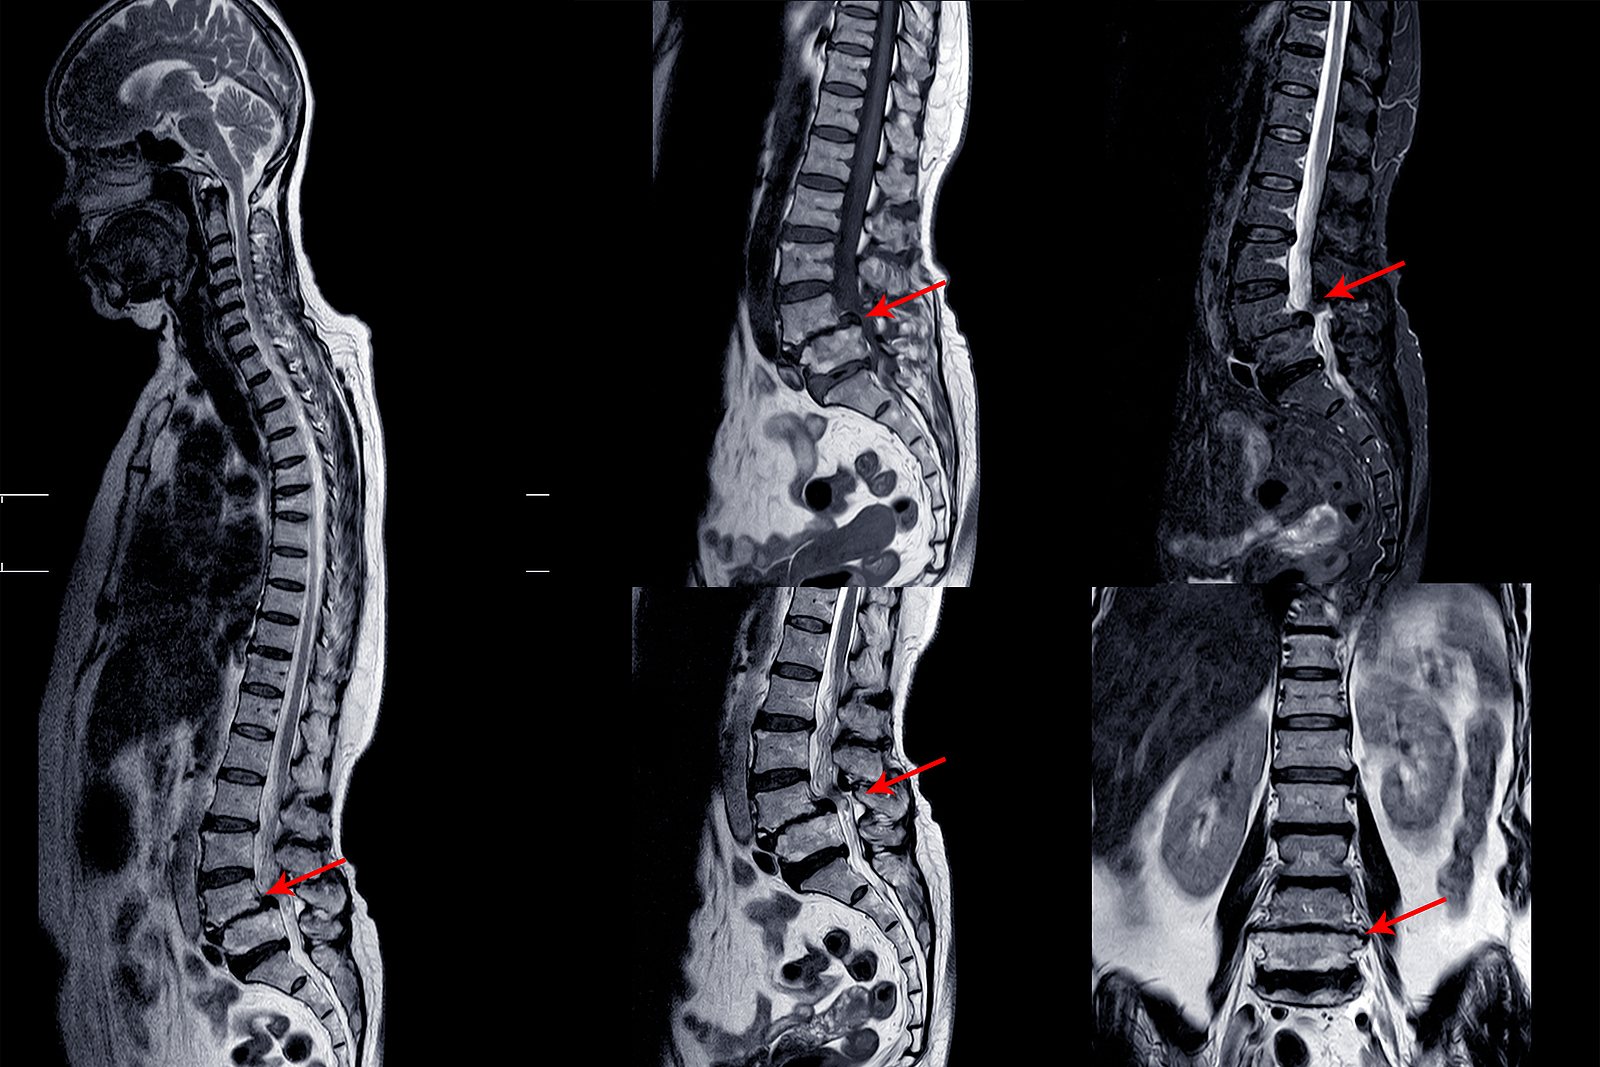

Magnetic Resonance Imaging (MRI)

An MRI scan uses magnetic waves (not radiation) to create pictures of the lumbar spine in sections called slices. The MRI scan shows the bones in the lumbar spine as well as soft tissue structures such as the discs, joints, and nerves. MRI scans are painless and don’t subject you to radiation as an x-ray does. MRI scans are the most common test for visualizing the lumbar spine after an x-ray has been taken. These tests may be recommended if your health care provider is concerned that surgery may be necessary.

In some cases, specialized MRIs that involve an injection of contrast dye may be recommended by your doctor to see specific structures. These special MRIs are performed following the intravenous injection of gadolinium-based dye. The contrast dye enhances image quality and can define some structures more than a regular MRI.